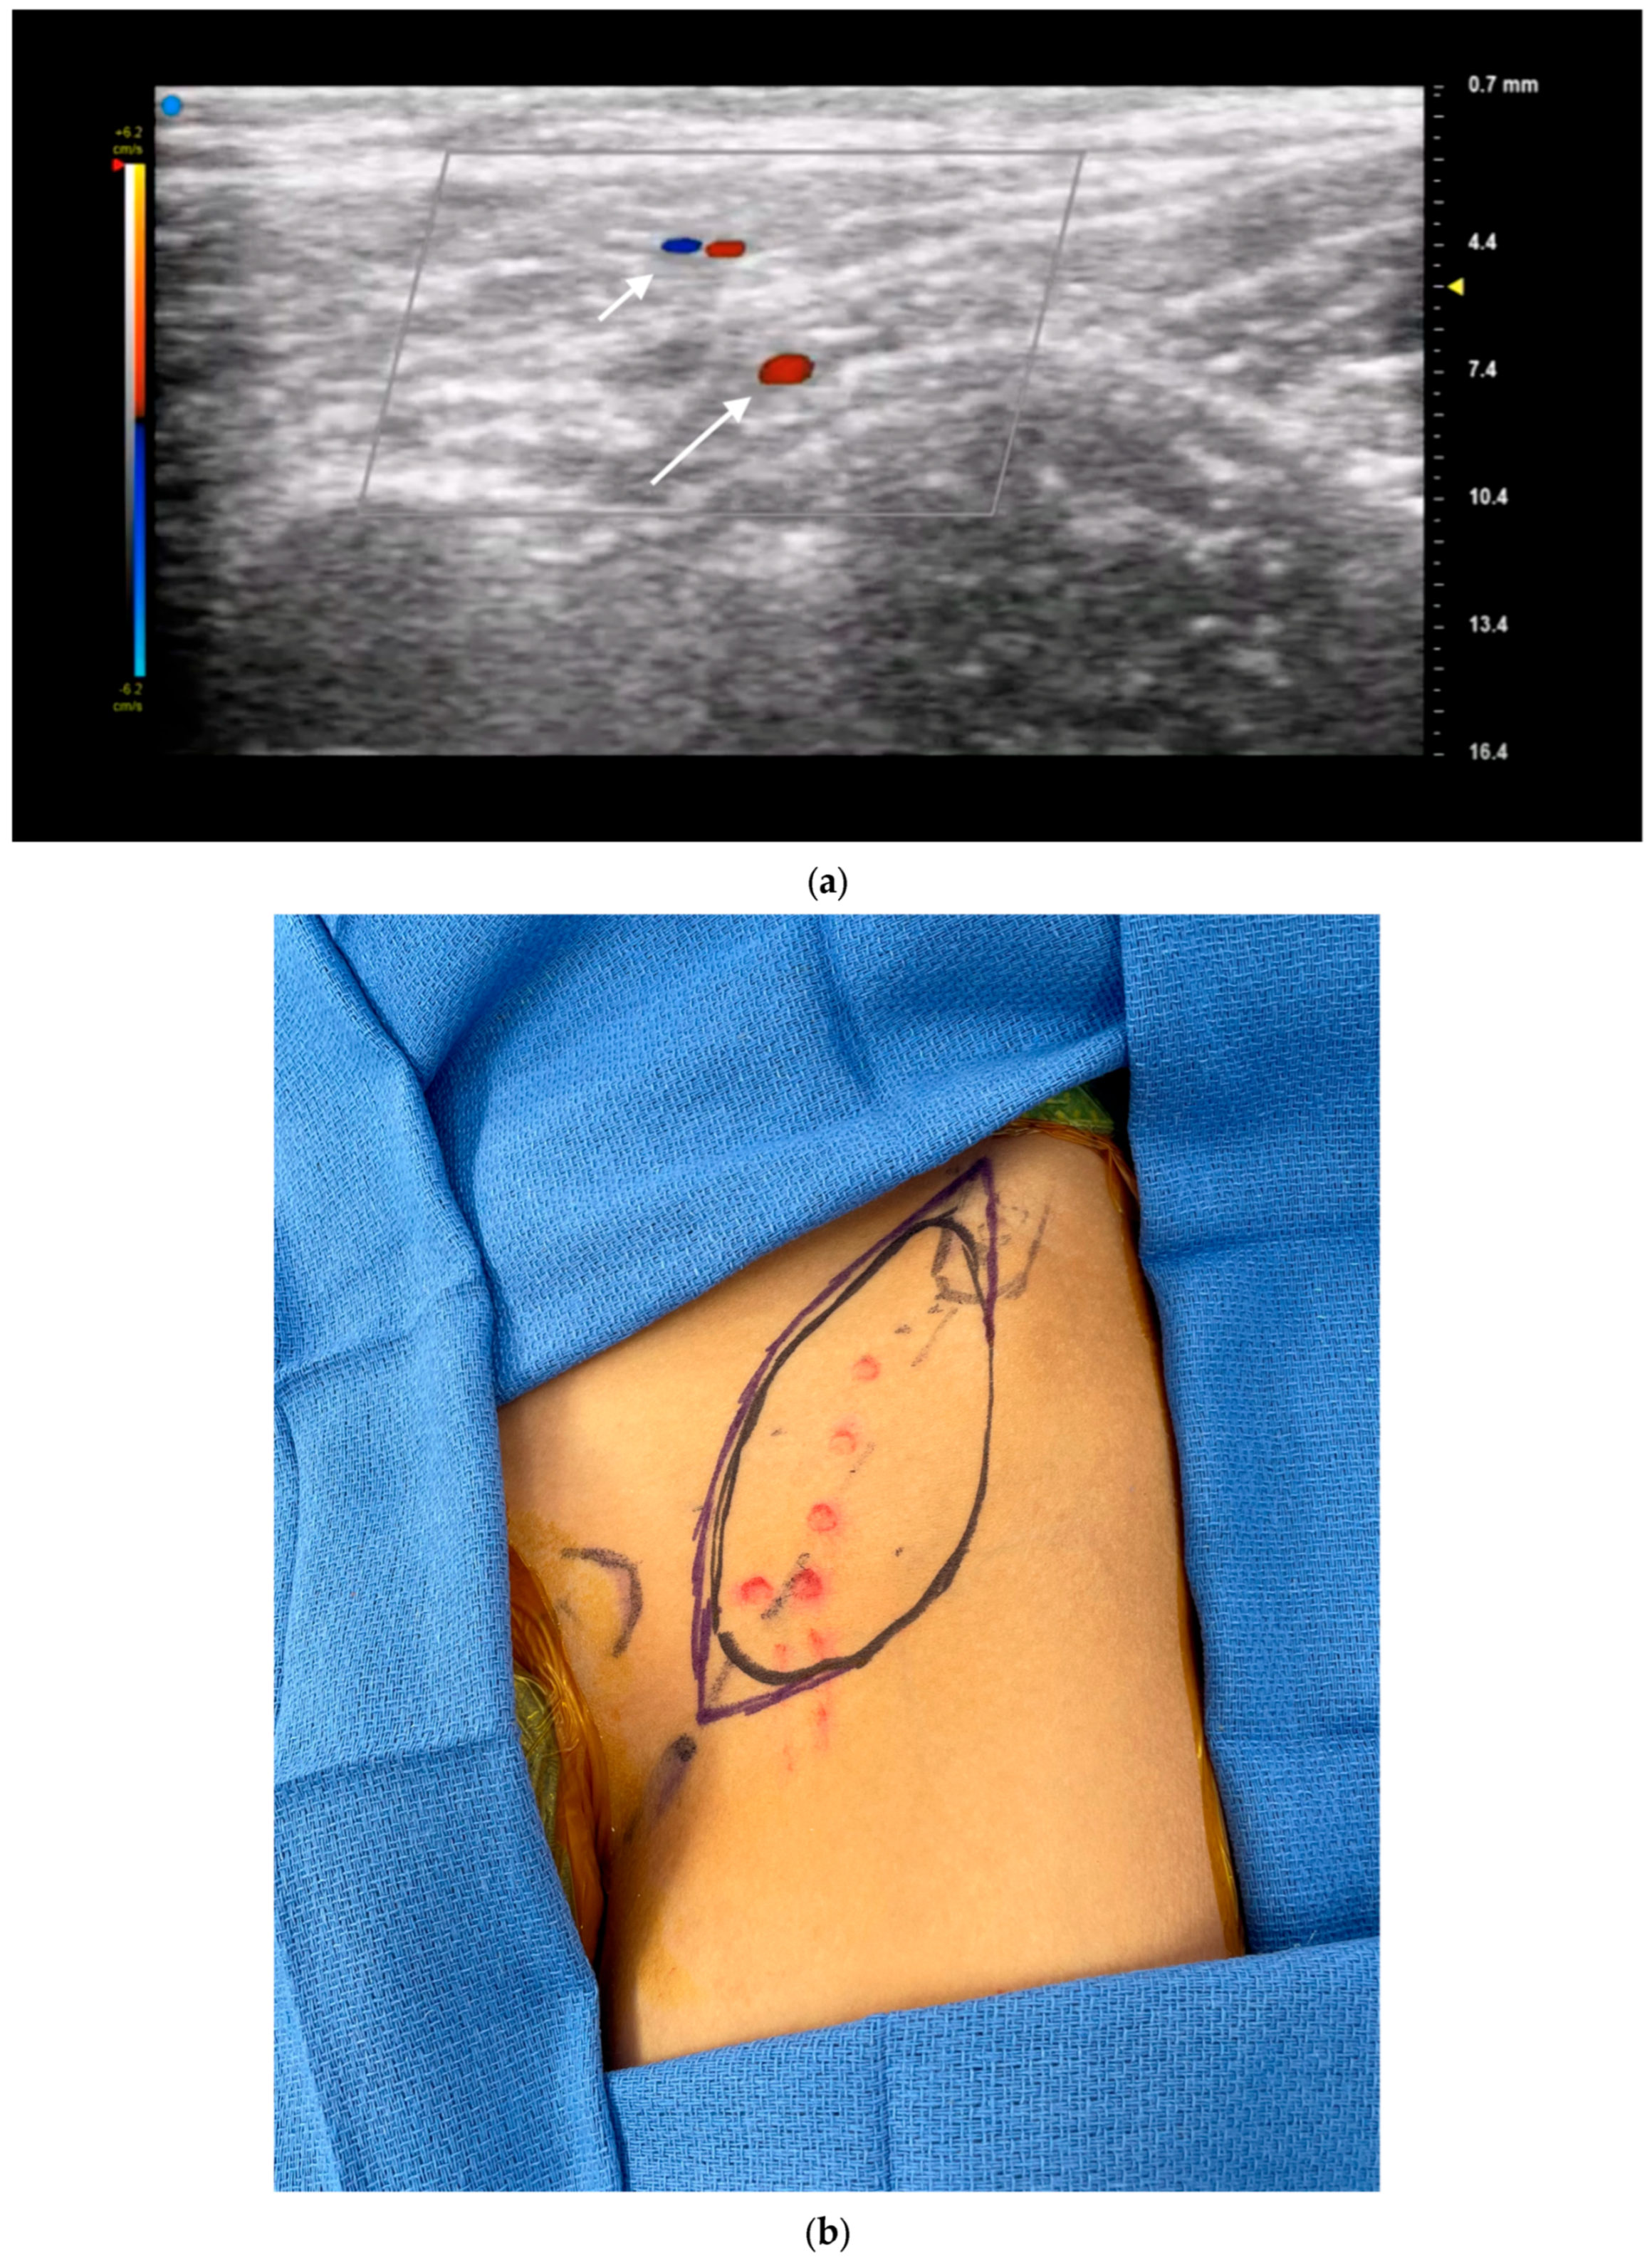

3.4. Lymphatic Surgery

- Czedik-Eysenberg, M.; Steinbacher, J.; Obermayer, B.; Yoshimatsu, H.; Hara, H.; Mihara, M.; Tzou, C.J.; Meng, S. Exclusive use of ultrasound for locating optimal LVA sites—A descriptive data analysis. J. Surg. Oncol. 2019, 121, 51–56. [Google Scholar] [CrossRef] [PubMed]

- Seki, Y.; Kajikawa, A.; Yamamoto, T.; Takeuchi, T.; Terashima, T.; Kurogi, N. The dynamic-lymphaticovenular anastomosis method for breast cancer treatment-related lymphedema: Creation of functional lymphaticovenular anastomoses with use of preoperative dynamic ultrasonography. J. Plast. Reconstr. Aesthetic Surg. 2019, 72, 62–70. [Google Scholar] [CrossRef] [PubMed]